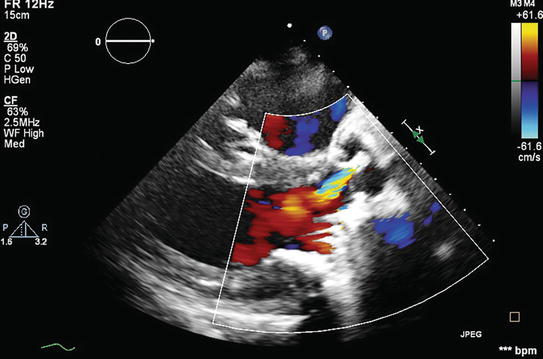

Paravalvular Regurgitation : Pvl represents pathologic regurgitation originating outside the sewing ring.